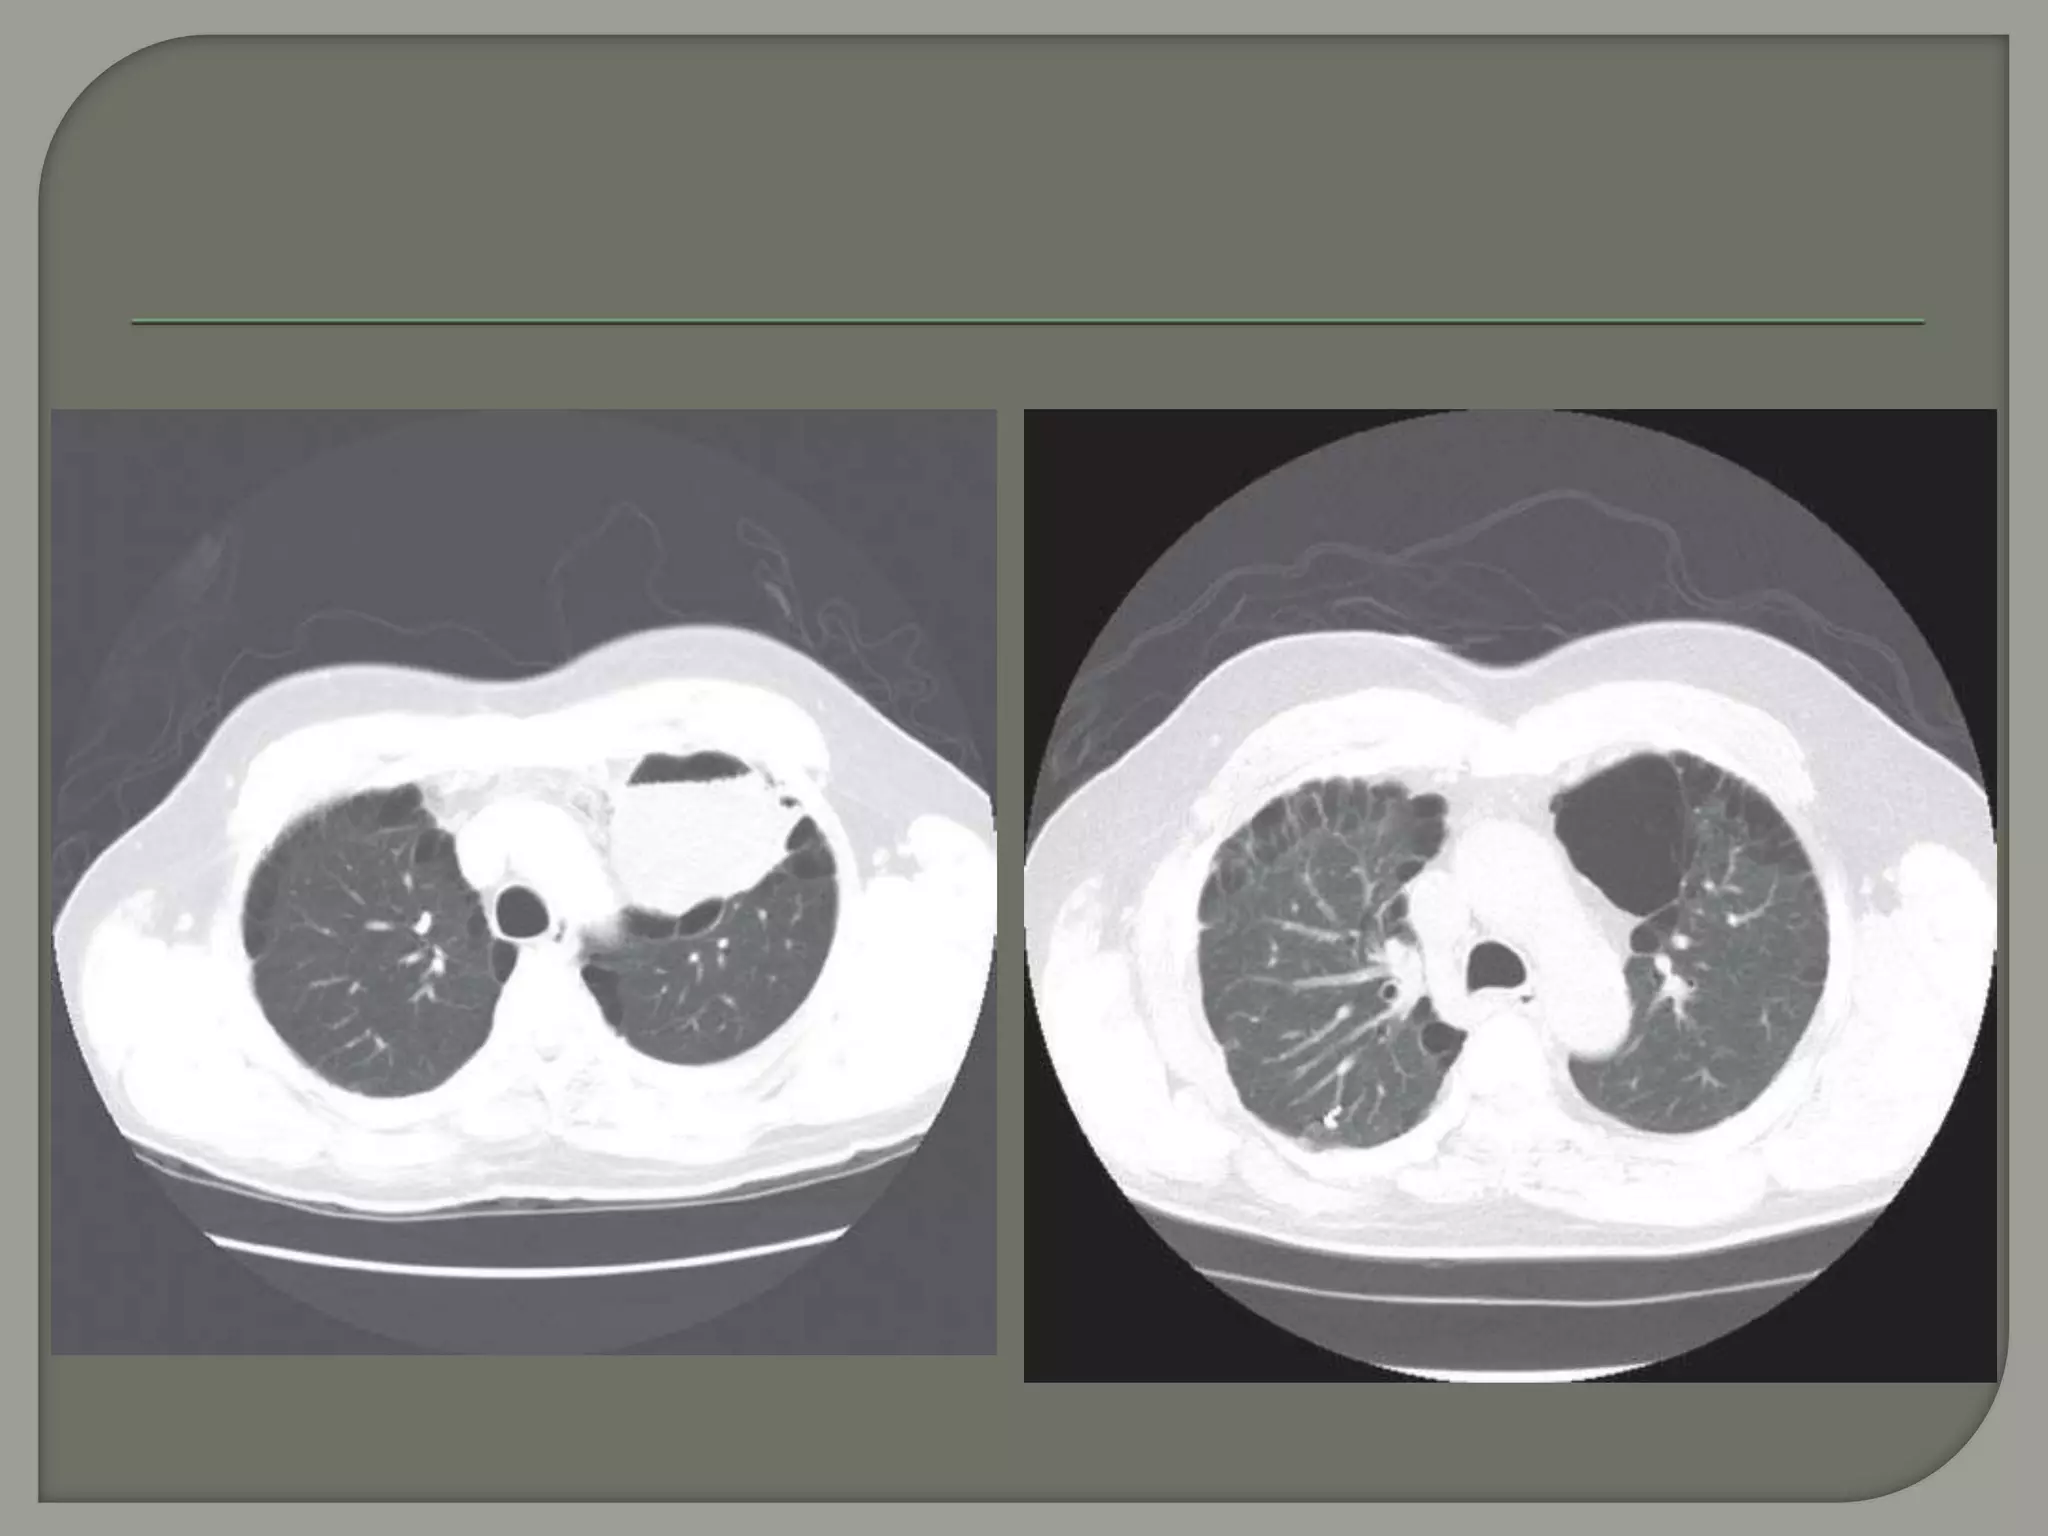

CT image of

the lungs

demonstrating

the right lower

lobe bulla with

compressed

lung

Giant bullae are predominantly located in the

upper lobes and generally subpleural.

However, in patients with

α1-antitrypsin deficiency, bullae are most

commonly located at the lung bases.